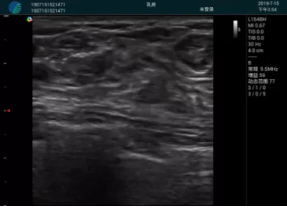

頸動(dòng)脈血流充盈飽滿,無外溢

肝內(nèi)血管顯示清晰,血流敏感無外溢

甲狀腺囊性結(jié)節(jié),囊壁鈣化,透聲好

甲狀腺囊性占位